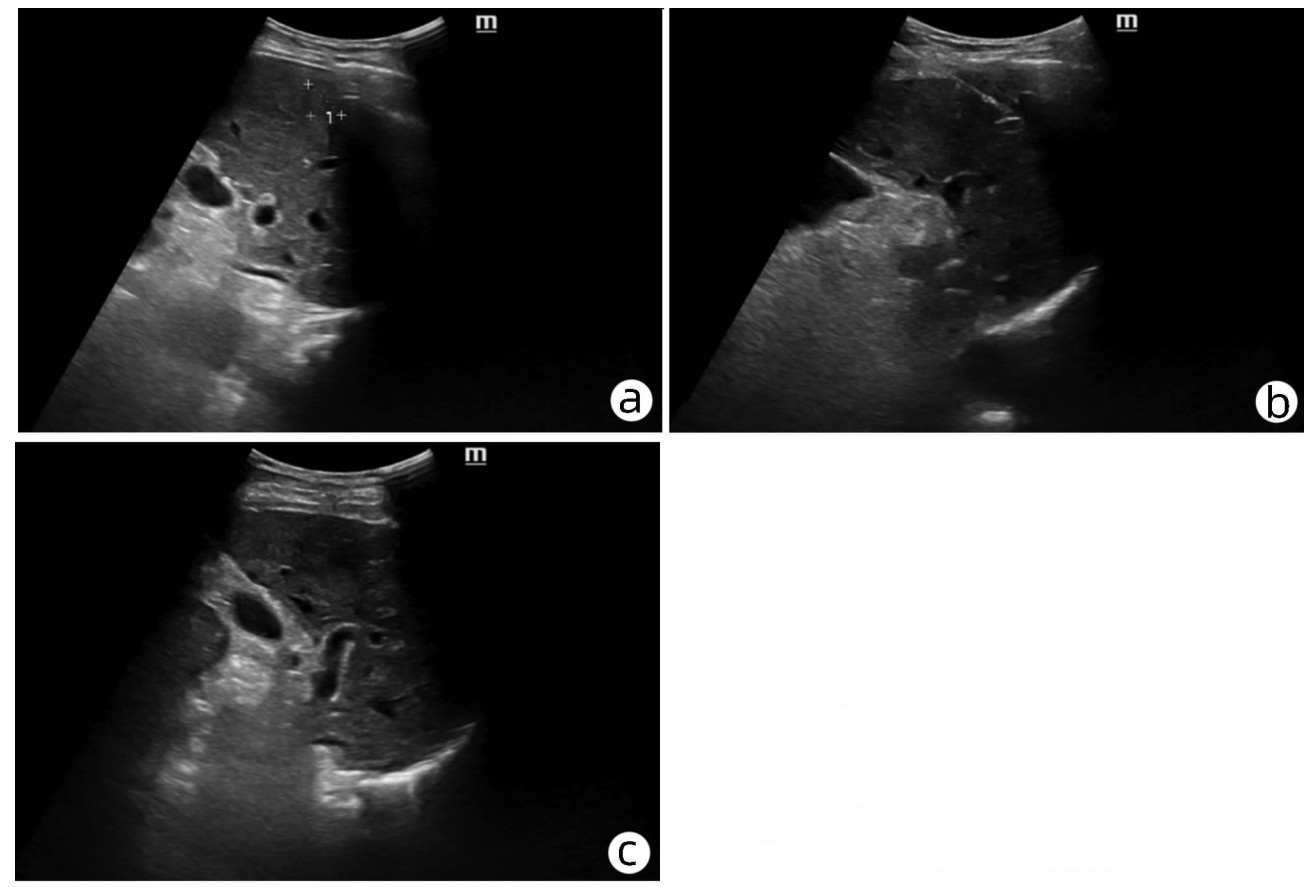

Hepatocellular carcinoma with bile duct tumor thrombus: A case report

Renjie LU, Fangfang SUN, Jie DU, Lirong ZHAO

2022, 38(8): 1872-1874. DOI: 10.3969/j.issn.1001-5256.2022.08.028

Abstract(831) HTML (461) PDF (3665KB)(88)